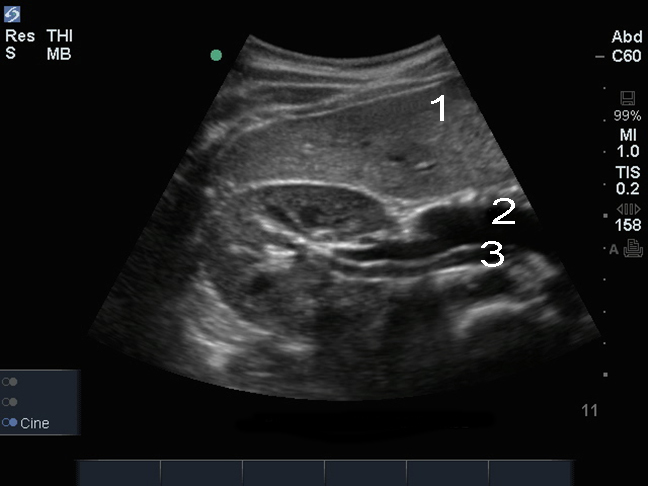

Imagen transversal del riñón derecho

Hígado

Vena

Arteria